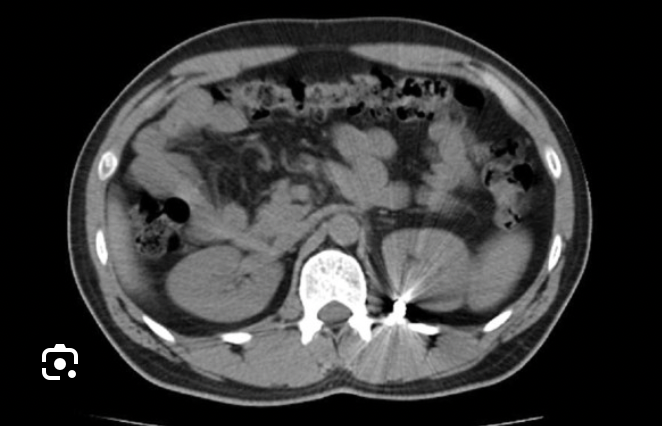

transverse

Which CT view?